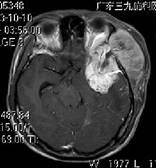

■ 术前MR

入院后次日行头颅MRI示桥脑及中脑异常信号,MRA示右侧大脑中动脉粗细不均(见图一)。腰穿脑脊液常规示白细胞计数(WBC)4×106/L,透明度透明,蛋白定性(Pandy`s 试验)±,颜色无色,脑脊液生化示总蛋白(TP)0.65g/L。进一步完善MRI弥散+增强+MRV+MRS示脑干病变范围较前略缩小,信号较前减弱,DWI示低或等信号,ADC示高信事情,病变弥散无受限,增强无强化(见图二),结合患者血压高达228/150mmhg,目前脑干病变考虑为高血压脑病引起的可逆性后部白质脑病。